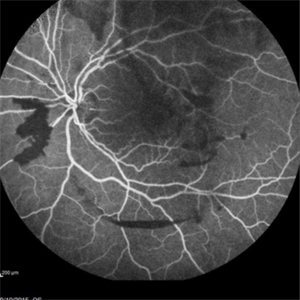

Angiography showed normal vessels posteriorly but severe capillary drop out throughout the periphery OU with scattered severe neovascularization at the edge of the capillary drop out peripherally.

Sickle Cell Retinopathy Sickle Cell RetinopathySep 13 2015 by Thomas A. Ciulla, MD, MBA, FASRS Angiography showed normal vessels posteriorly but severe capillary drop out throughout the periphery OU with scattered severe neovascularization at the edge of the capillary drop out peripherally. Note the preretinal and vitreous hemorrhage obscuring the view of the retinal vasculature. Photographer: Thomas Steele Condition/keywords: peripheral retinal neovascularization, sea fan, sickle cell retinopathy